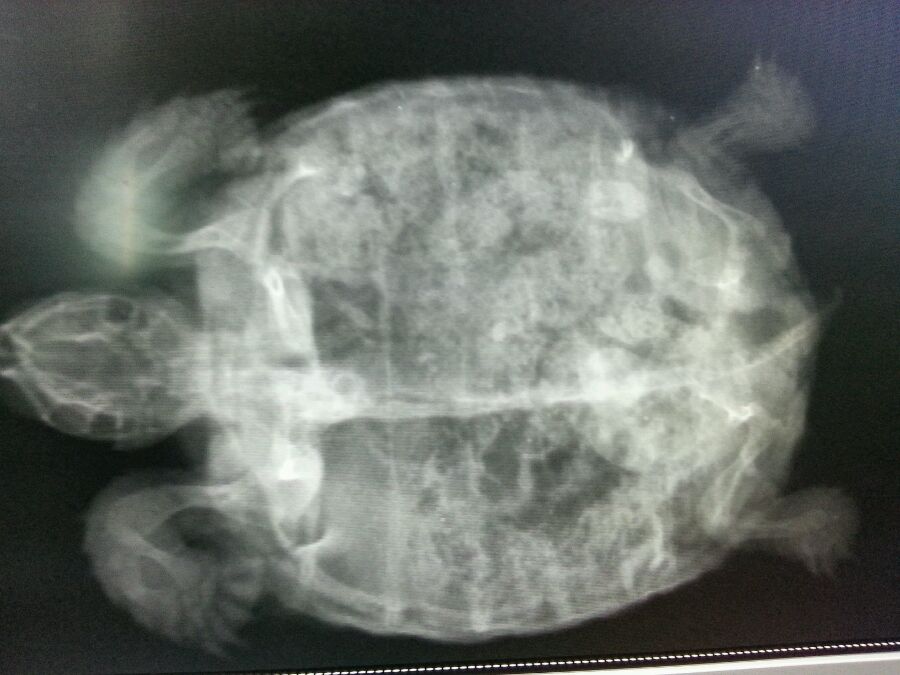

今天中午排了巨多石头,下午拍了个片,大家看看有结石吗

苏卡达陆龟吧